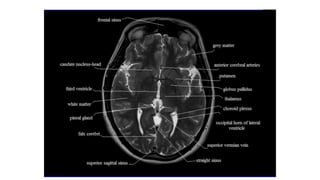

How to read a MRI

• • We should know what structures are seen in which sections of brain

so that we can identify the abnormality.

• • Showing you sections of adult brain and structures seen in them.

• • For neonatologists dealing with asphyxial injuries we should focus

on sections involving basal ganglia and thalami as they are primarily

involved in HIE.

• • You can only interpret MRI if you what structure to see in which

disorders and which sections to see it in.